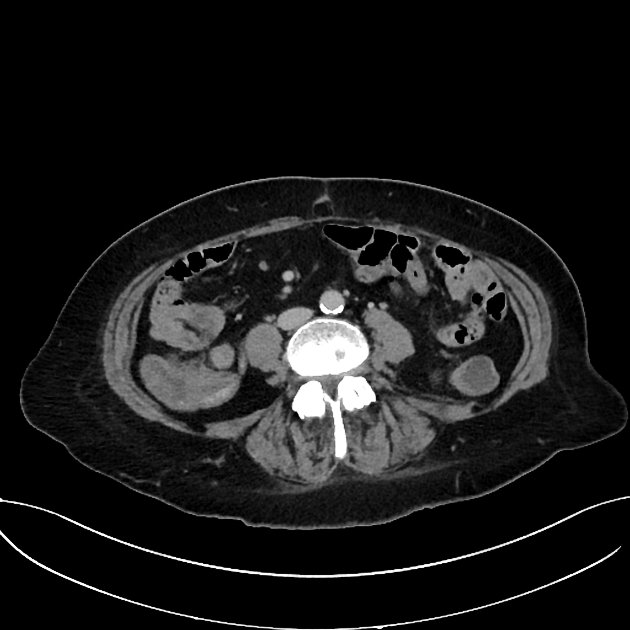

CT Bleeding Study

A patient presents with acute hypotension and hematochezia. An estimated 2L of blood loss was recorded in the ED. The patient was referred to general surgery. The bleeding stopped, and the patient remained hemodynamically stable. A colonoscopy was arranged. CT findings suggest an unusual cause of lower gastrointestinal bleeding. Based on the provided CT scan and case history, what is the most likely diagnosis?

Correct answer is Appendiceal hemorrhage due to angiodysplasia